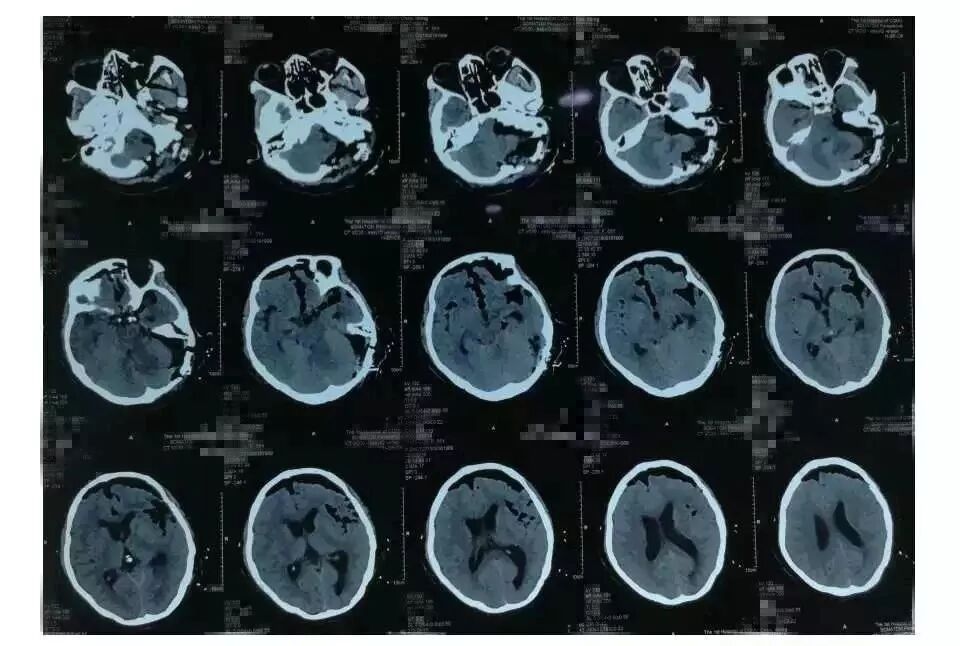

术后6小时患者头颅CT